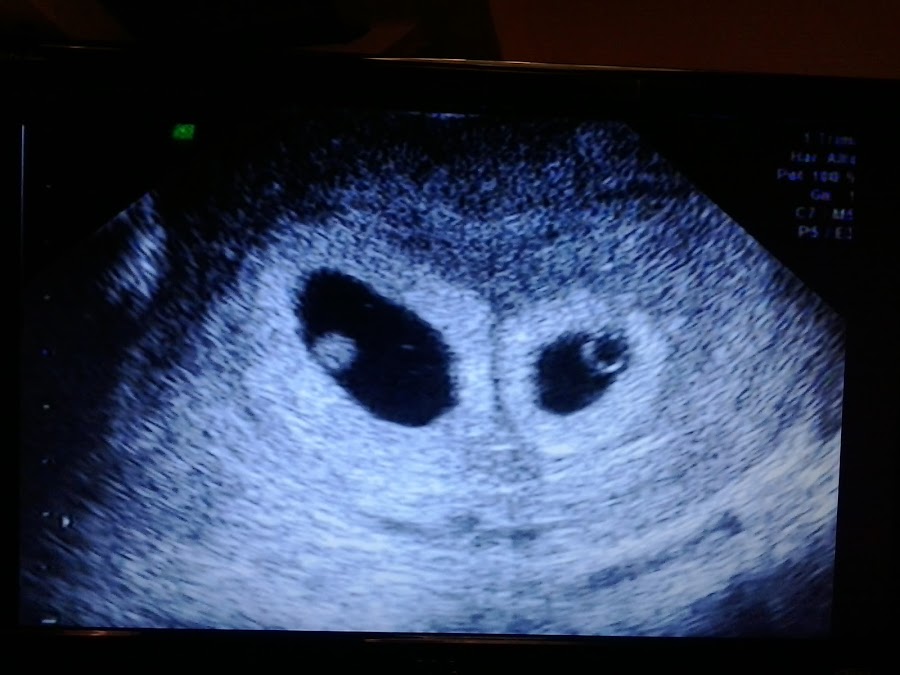

A veces uno mira la televisión y ve cómo se van moviendo los bebes en el vientre en las películas o en series, pero otra cosa es poder ver y escuchar tus propios bebes, escuchar sus latidos, ver como se mueven –es algo hermoso e indescriptible, yo he tomado fotos desde las 4 semanas y también tengo el video de los primeros movimiento y latidos que nos mostró el doctor. Me acuerdo que camino a casa no me cansaba de estar mirando el video, es realmente impresionante cómo está de avanzada la tecnología.